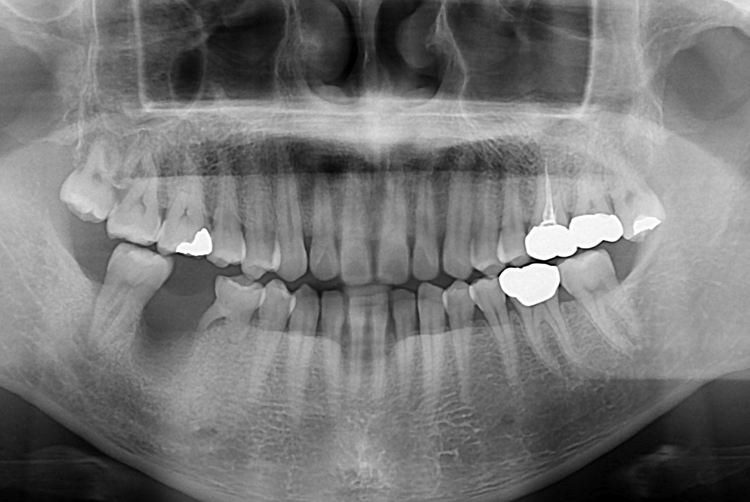

[임플란트] 어금니 임플란트

치료전 : 2019-08-27